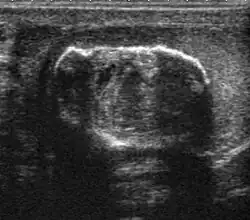

The incidence of infertility is decreased if surgical orchiopexy is carried out before the 1–3 years but the risk of malignancy does not change. Because of the superficial location of the inguinal canal in children, sonography of undescended testes should be performed with a high frequency transducer. At ultrasound, the undescended testis usually appears small, less echogenic than the contralateral normal testis and usually located in the inguinal region [Fig. 29]. With color Doppler, the vascularity of the undescended testis is poor.

-

Fig. 29. Undescended testis. (a) Normal testis in the scrotum. (b) Atrophic and decreased echogenicity of the contralateral testis of the same patient seen in the inguinal region.